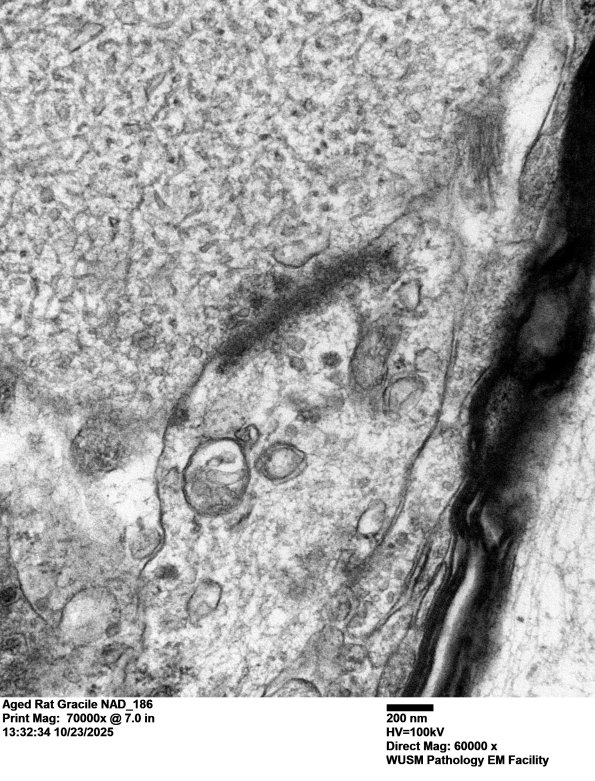

A particularly photogenic dystrophic presynaptic axon containing tubulovesicular elements. (electron micrographs)